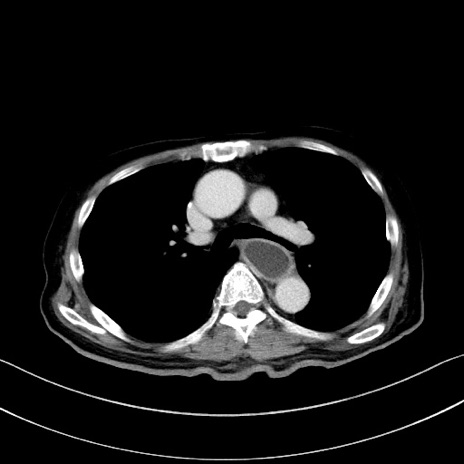

症例28(横断像)

【症例】60歳代男性

【主訴】嘔吐

【現病歴】胃癌にて胃全摘後。食思不振が悪化し、夜中に嘔吐することがある。

【既往歴】胃癌、胃全摘、脾摘、胆摘後

【データ】WBC 5900、CRP 10.56